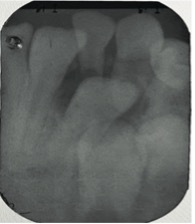

En el examen clínico intraoral, se observó dentición mixta, todos los dientes limpios, sin embargo, con maloclusión, por esa razón el paciente fue referido para evaluación y tratamiento ortopédico. Conforme la mamá había reportado, los incisivos laterales primarios inferiores estaban en oclusión (Figura 1) y sin movilidad. A través de la radiografía periapical en la región de los incisivos laterales inferiores (Figuras 2 y 3), fue observado que los gérmenes de los incisivos laterales inferiores permanentes se encontraban en la etapa 8 de Nolla, entonces, deberían estar estallando en la cavidad oral.

Figura 1: Fotografía intraoral oclusal de la arcada inferior: Se observa la presencia de los incisivos laterales primarios inferiores.